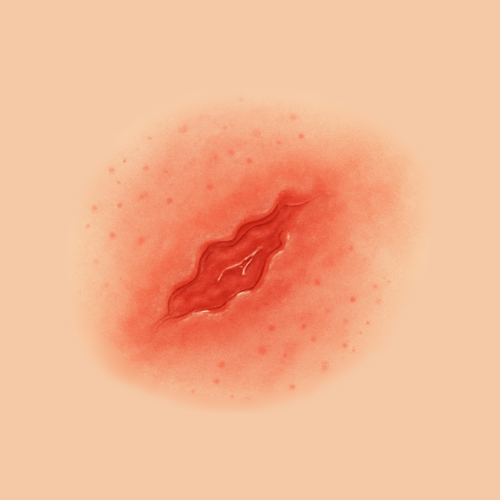

Find Relief by Symptom or Skin Concern

EMUAID is designed to relieve symptoms from over 100 difficult-to-treat conditions like eczema, psoriasis, nail fungus, hemorrhoids, shingles, acne, rashes, burns, cellulitis, and more. If it's red, itchy, cracked, painful, or inflamed- EMUAID may help.

Clean and dry the affected area, then apply a thin layer of EMUAID 1-3 times daily. Do not rub in completely- let it absorb naturally. For best results, cover with a bandage or clean wrap if treating open wounds or cracked skin.